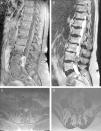

CasoPaciente de 68 años valorada tras presentar lumbociática de difícil control analgésico objetivándose una lesión intradural-extramedular lumbar. La lesión, en relación al filum terminal, fue resecada parcialmente siendo el diagnóstico anatomopatológico de tumor neuroendocrino bien diferenciado primario (carcinoide). Tras valoración multidisciplinaria, se decidió tratamiento radioterápico estereotáctico fraccionado. En los sucesivos controles no se evidenció progresión ni diseminación metastásica.

CaseA 68-years old patient was assessed after presenting lower back pain and sciatica with ineffective pain relief. The patient presented an intradural-extramedullary lumbar lesion arising from the filum terminale, which was partially resected. The pathology diagnosis was a well-differentiated primary neuroendocrine tumor (carcinoid tumor). After a multidisciplinary evaluation, fractionated stereotactic radiotherapy was administered. No progression or metastatic spread was observed in successive assessments.